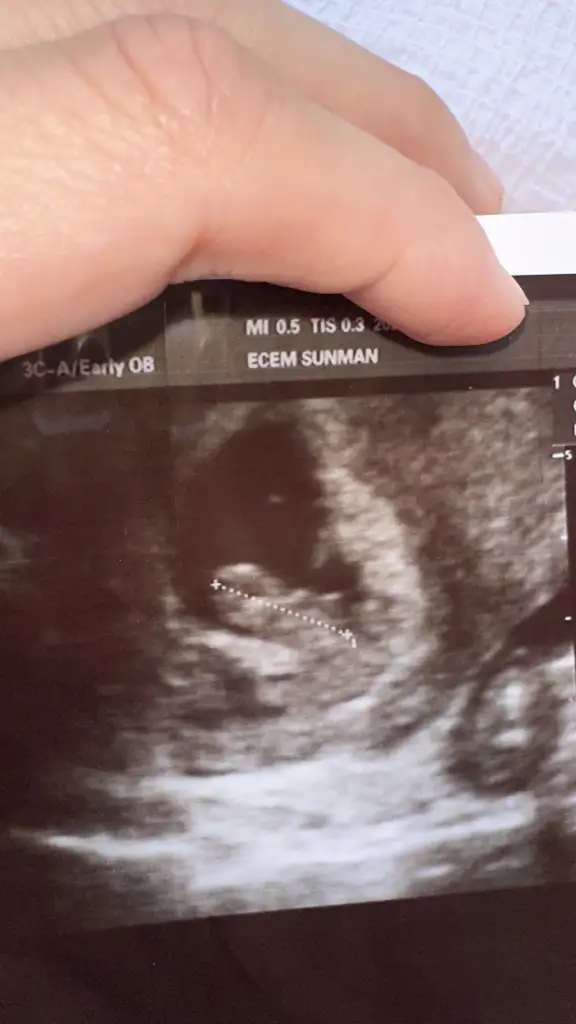

Benim attığım ultrason görüntülerine göre yorumlar mısın rica etsemtahmını bence kız :)

Erkeğe benziyor canımbenim için de bakar mısınız ilki 6 +4 ikinci fotoğraf 8+3 sonuncusu 10+1 Eki Görüntüle 3623528 Eki Görüntüle 3623526 Eki Görüntüle 3623525

Sağlıkla kucağımıza alalım inşallah . Bende erkek hissediyorum nedense.Erkeğe benziyor canım